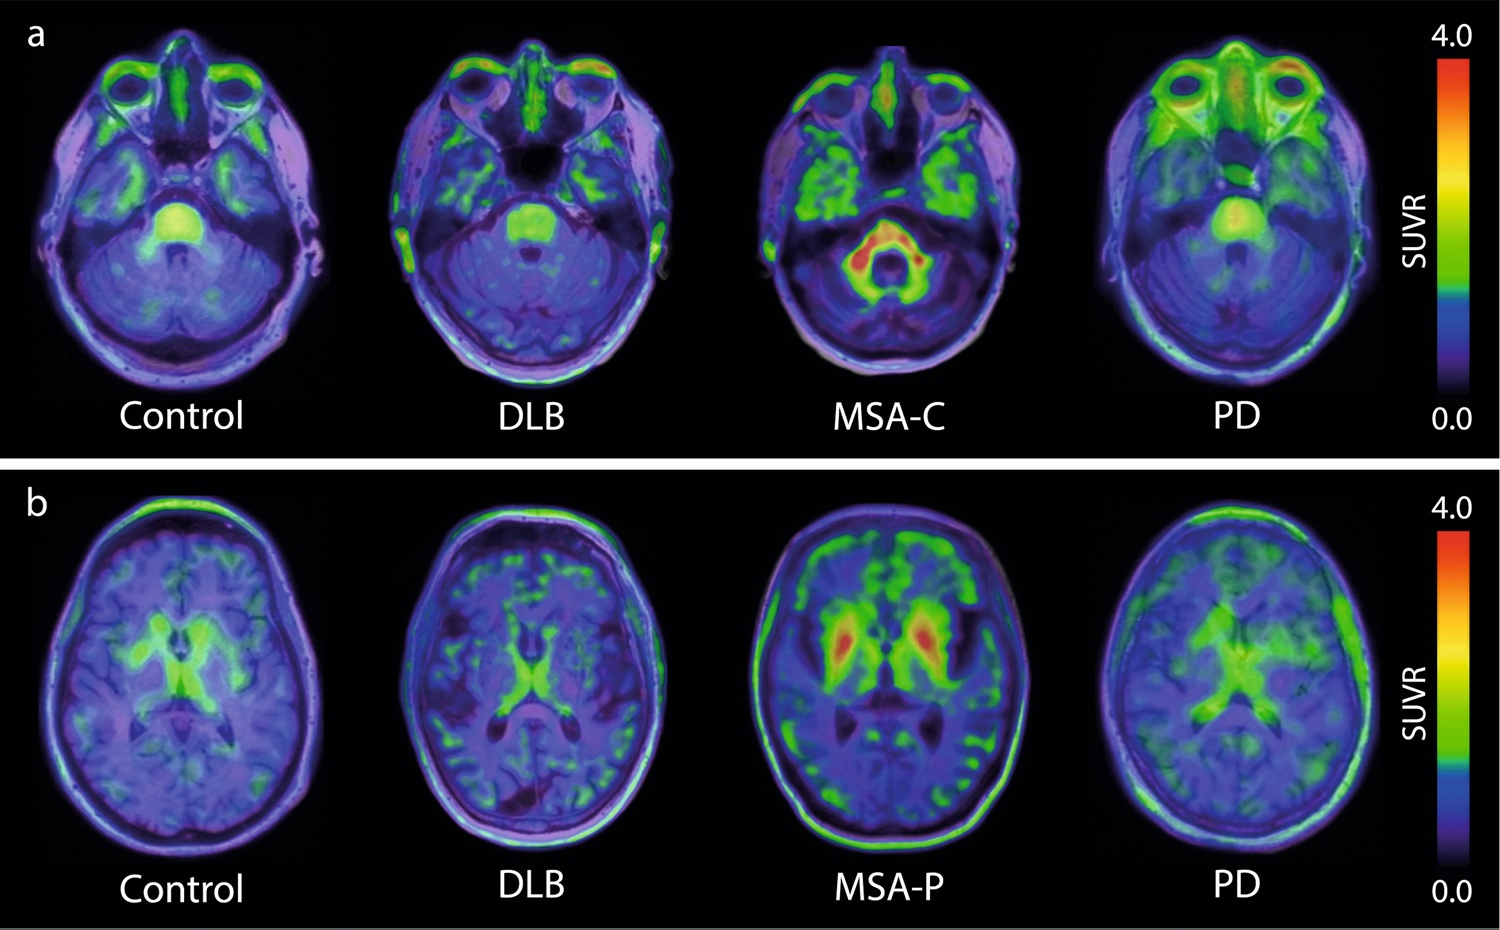

Brain scans taken with the tracer strongly indicate the signal specificity for alpha-synuclein in MSA patients, compared with healthy volunteers and patients with other alpha-synucleinopathies, like Parkinson's disease and Lew Body Dementia. The results represent the potential for earlier and more reliable differentiation for MSA, lead researcher, Dr. Oskar Hansson, PhD, of Lund University, said in a press release.

Furthermore, the tracer showed target engagement in vivo in alpha-synucleinopathies with a pharmacokinetic and safety profile suitable to be developed as a human brain PET imaging agent. Specifically, the ACI-12589 data showed enhanced contrast and alpha-synuclein target specificity in those with MSA. Tracer retention was highest in areas affected by MSA disease processes, particularly cerebellar white matter, according to the trial results.